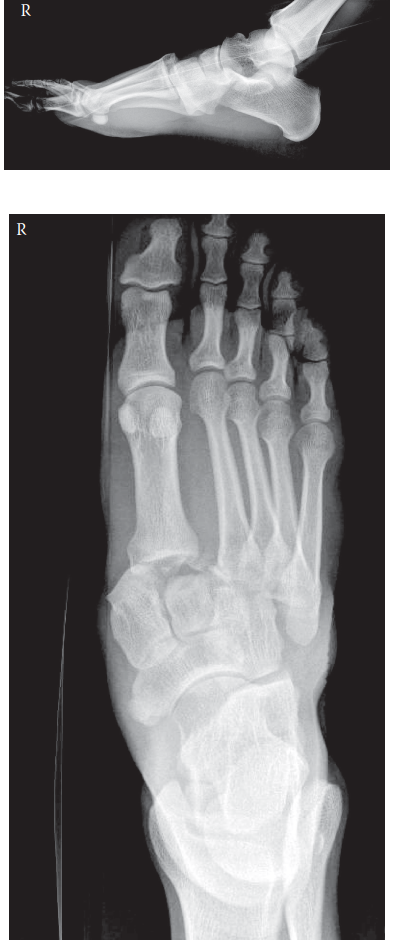

These are radiographs as well as a clinical photograph of the right foot of a 68-year-old man who stumbled do…

1. Describe what you see and your initial management in the emergency department. This is a clinical photogra…